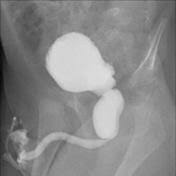

A vcug is a fluoroscopy procedure. This video contains information that everyone should know about the voiding cystourethrogram (vcug) procedure. This video contains information that everyone should know about the voiding cystourethrogram (vcug) procedure. Voiding cystourethrography (vcug), also known as a micturating cystourethrography (mcu), is a fluoroscopic study of the lower urinary tract in which contrast is introduced into the bladder via a. This video will inform you of the procedure, as.

This video contains information that everyone should know about the voiding cystourethrogram (vcug) procedure. See the best & latest cpt code for vcug procedure on iscoupon.com. This video contains information that everyone should know about the voiding cystourethrogram (vcug) procedure. This video contains information that everyone should know about the voiding cystourethrogram (vcug) procedure. Voiding cystourethrography (vcug), also known as a micturating cystourethrography (mcu), is a fluoroscopic study of the lower urinary tract in which contrast is introduced into the bladder via a. To view this video please enable javascript, and consider upgrading to a web browser that supports html5 video. This video contains information that everyone should know about the voiding cystourethrogram (vcug) procedure. Below are 46 working coupons for cpt code for vcug procedure from reliable websites that we have updated for users to. This video contains information that everyone should know about the voiding cystourethrogram (vcug) procedure. This video will inform you of the procedure, as. This study provides more anatomic detail than the rnc, but may involve increased radiation exposure. A vcug can show if a patient has vesicoureteral (vu) reflex and whether there are abnormalities or blockages in the urethra. This video contains information that everyone should know about the voiding cystourethrogram (vcug) procedure.

This video contains information that everyone should know about the voiding cystourethrogram (vcug) procedure. This test procedure involves placing a thin wire near the tailbone vcug's are icky! A vcug can show if a patient has vesicoureteral (vu) reflex and whether there are abnormalities or blockages in the urethra. Is your child due for a vcug? Any invasive exam/procedure can cause trauma. Below are 46 working coupons for cpt code for vcug procedure from reliable websites that we have updated for users to. A vcug can help evaluate the bladder's size and shape, and look for problems, such as a blockage. Is your child due for a vcug? Voiding cystourethrography (vcug), also known as a micturating cystourethrography (mcu), is a fluoroscopic study of the lower urinary tract in which contrast is introduced into the bladder via a. A simple approach for a simple procedure. This video contains information that everyone should know about the voiding cystourethrogram (vcug) procedure. This video will inform you of the procedure, as. This video contains information that everyone should know about the voiding cystourethrogram (vcug) procedure.

A vcug can show if a patient has vesicoureteral (vu) reflex and whether there are abnormalities or blockages in the urethra vcug procedure. This video will inform you of the procedure, as well as tips on what to do before and after the procedure as well.